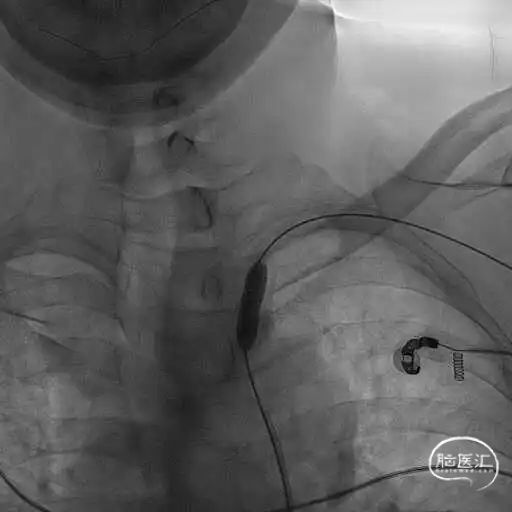

8F Guiding+5F MPA同轴置于左侧锁骨下动脉残端处,反复尝试Command 190cm及Command ES 190cm导丝配合Rebar-18微导管,导丝无法进入真腔,更换Connect 195cm导丝尝试后顺利进入真腔,使用小球囊预扩, Guiding跟到病变远端。

更换Supracore导丝,使用雅培 5*40mm Armada35 球囊扩张后在闭塞起始部植入8*29mm Omnilink支架。

使用雅培 Command导丝顺利超选进入左椎V2段,冠脉3.0*12mm球囊进行扩张,在V18导丝的支撑下,在左侧椎动脉起始部植入一枚雅培4.5*15mm Herculink支架。支架植入后,造影提示椎动脉狭窄得到明显改善。